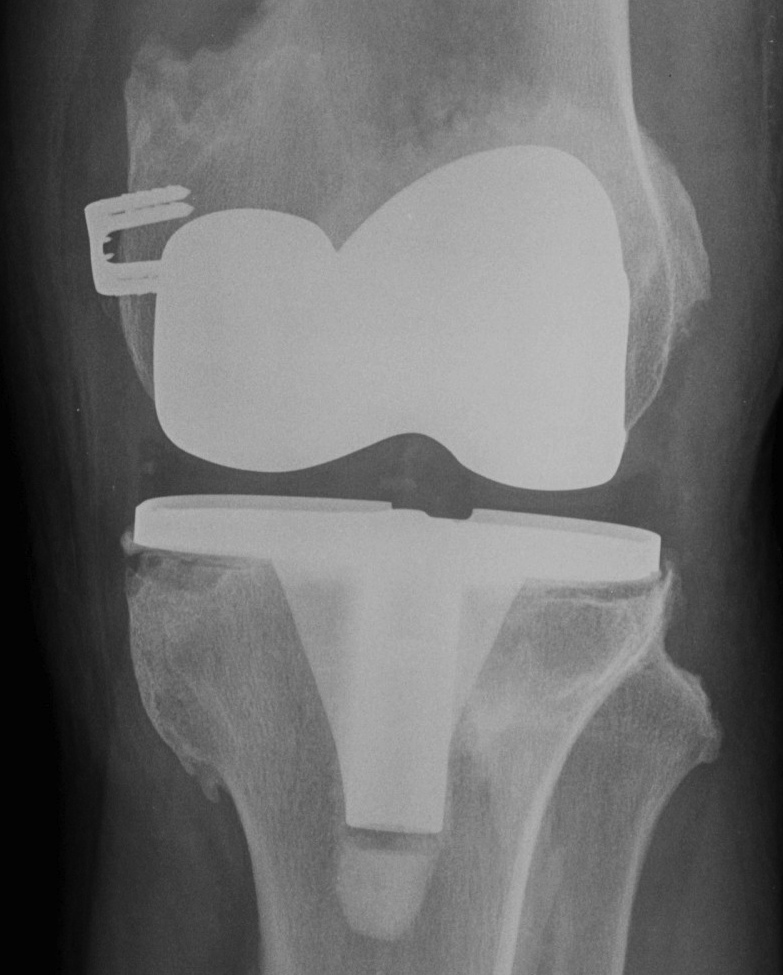

- post ACL reconstruction / TKR